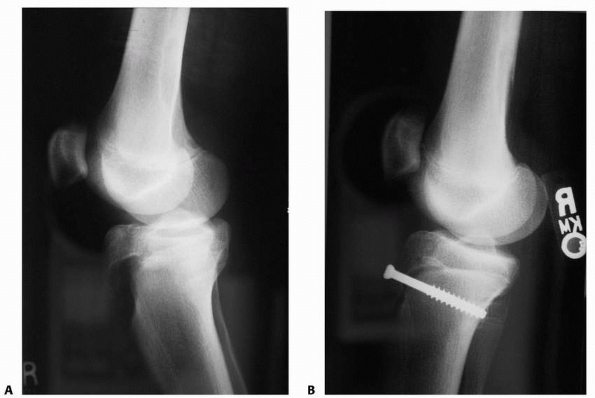

FIGURE 23-4 A.

In a Salter-Harris type II fracture, the side where the fracture occurred through the physis fails in tension, with disruption of the periosteum. The side of the fracture with the Thurstan-Holland fragment failed in compression, with the periosteum usually intact. The intact periosteum can be used for fracture reduction. B. With fracture reduction, the periosteum may become interposed within the fracture site, preventing an anatomic reduction |

Salter-Harris type I fractures generally extend through the

hypertrophic zone and the zone of provisional calcification without

traversing the germinal layers. Salter-Harris type II fractures exit

through the

metaphysis with a spike of metaphyseal bone attached to the epiphysis on the compression side (Thurstan-Holland fragment) (Fig. 23-4A).

In any type of epiphyseal fracture, a flap of torn periosteum may

become interposed between the fragments and prevent reduction (see Fig. 23-4B). Salter-Harris types III and IV fractures cross the entire physis vertically and enter the joint through articular cartilage.